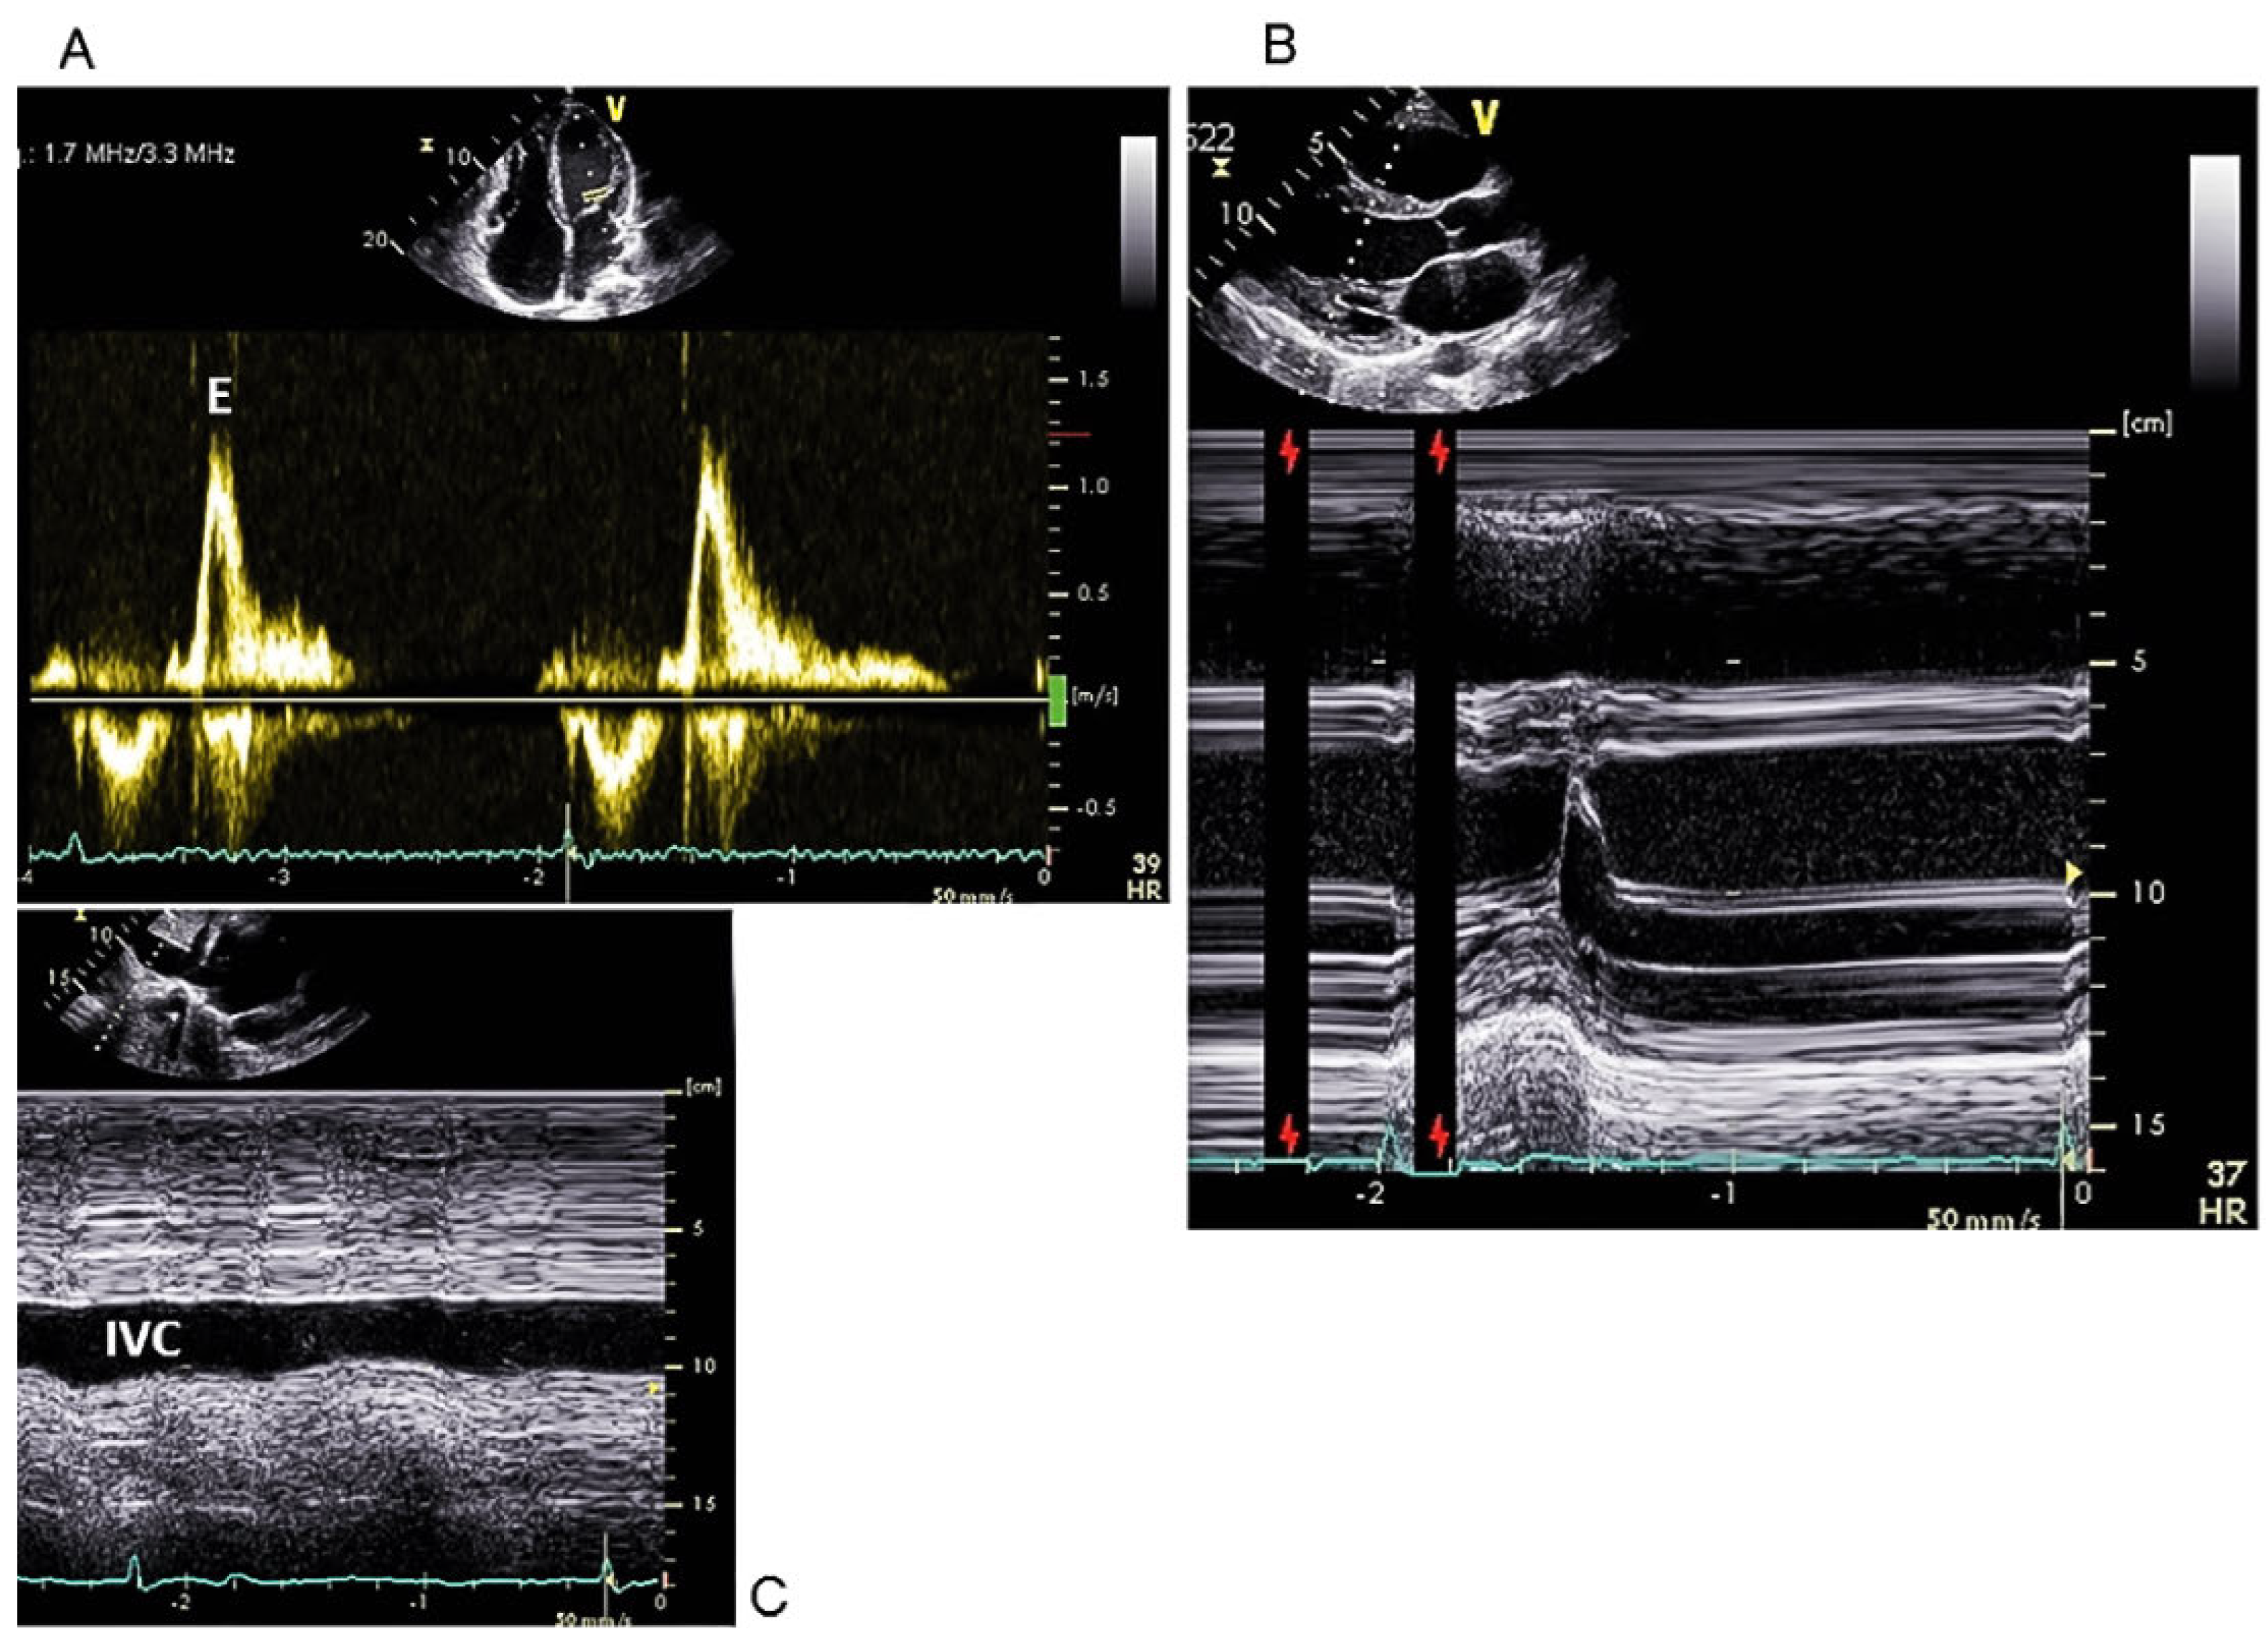

Case report

A 37-year-old male patient was referred to our cardiology division with a longstanding and worsening history of short episodes of dizziness and reduced effort tolerance. He denied any syncope, palpitations or chest pain. His medical history was unremarkable and he took no medication. Family history was negative for cardiac diseases at a young age or premature sudden death. On clinical examination, the patient appeared in good general condition. He was bradycardic at 40 bpm and normotensive; heart and lung auscultation was normal, the jugular veins distended. The resting ECG displayed a junctional rhythm at 35 bpm with complete right bundle-branch block and no atrial electrical activity (Figure 1). A chest X-ray showed cardiomegaly without pulmonary congestion. During a 24-hour Holter ECG, no atrial activity was discernible and a constant bradycardic junctional rhythm was noted, with a mean heart rate of 36 bpm. Moreover, 83 episodes of asystole lasting more than 3 seconds were recorded, of which 11 lasted more than 6 seconds, with the longest episode in the night being of 10.5 seconds duration (Figure 2). There were no serious ventricular arrhythmias and only 62 isolated premature ventricular beats were registered. An exercise stress test confirmed the reduced effort tolerance and absent atrial electrical activity, and revealed a severe chronotropic incompetence with maximum junctional heart rate of 88 bpm (Figure 3). The echocardiogram showed a moderate dilatation of all cardiac chambers (Figure 4) with normal biventricular systolic function, absent mechanical activity of both atria, and systemic congestion (as shown in Figure 5 for the left atrium). Brain natriuretic peptide was moderately elevated (563 ng/l, reference range <100 ng/l), as were cholestatic enzymes (gammaglutamyltransferase [GGT] 210 U/l, reference range <71 U/l). Cardiac magnetic resonance imaging confirmed the moderate dilatation of the heart chambers with normal biventricular systolic function and did not reveal ventricular myocardial fibrosis or evident atrial parietal thickening or fibrosis. An intracavitary thrombus, particularly in the left atrial appendage, was also excluded. An electrophysiological study and genetic analysis were refused by the patient. Nevertheless, all clinical and paraclinical findings were consistent with a total atrial standstill, possibly idiopathic. Because of the severe symptomatic bradycardia, a pacemaker was implanted. During the procedure, no electrical activity was recorded in the whole right atrium and no atrial capture was obtained even at maximal output (10 volts, 1.5 msec.). Therefore, a single-chamber ventricular pacemaker was implanted. Oral anticoagulation therapy was considered, but we decided against it in the face of a CHA2DS2-VASc score of 0 and the absence of left atrial appendage thrombus.

Atrial standstill, first described by Chavez et al. in 1946 [1], is characterised by the absence of electrical and mechanical activity of the atria. The ECG usually displays no discernible P waves and a regular bradycardic junctional rhythm [2,3]. Effort-related chronotropic incompetence and transient asystole are common, as in our patient [4,5]. The atrial mechanical dysfunction can be readily detected on an echocardiogram by the absence of an A-wave in transmitral or transtricuspid flow, by the lack of telediastolic opening of the mitral (or tricuspid) valve, as our case nicely showed, and by the absence of active atrial contraction in tissue Doppler imaging [2,3]. Atrial standstill is a rare but serious condition, since the longstanding profound bradycardia and the loss of atrial function can have severe haemodynamic consequences, potentially leading to syncope, heart failure and, very rarely, sudden cardiac death. Cardiac arrest can be caused by extreme bradycardia or pause-related malignant ventricular arrhythmias, particularly when atrial standstill is associated with an underlying cardiopathy [6,7,8,9]. Moreover, the dysfunctional and dilated atria with consequent blood stasis can cause thromboembolic events, as in atrial fibrillation [5,6]. Our patient complained of dizziness, effort intolerance and systemic congestion.

Figure 4. Parasternal long axis (A) and apical four chamber (B) echocardiogram views showing a moderate dilatation of all cardiac chambers (left ventricular end-diastolic diameter of 64 mm, right ventricular end-diastolic basal diameter of 50 mm, left atrial antero-posterior diameter of 52 mm). LV = left ventricle; RV = right ventricle; LA = left atrium; RA = right atrium; RVOT = right ventricular outflow tract.